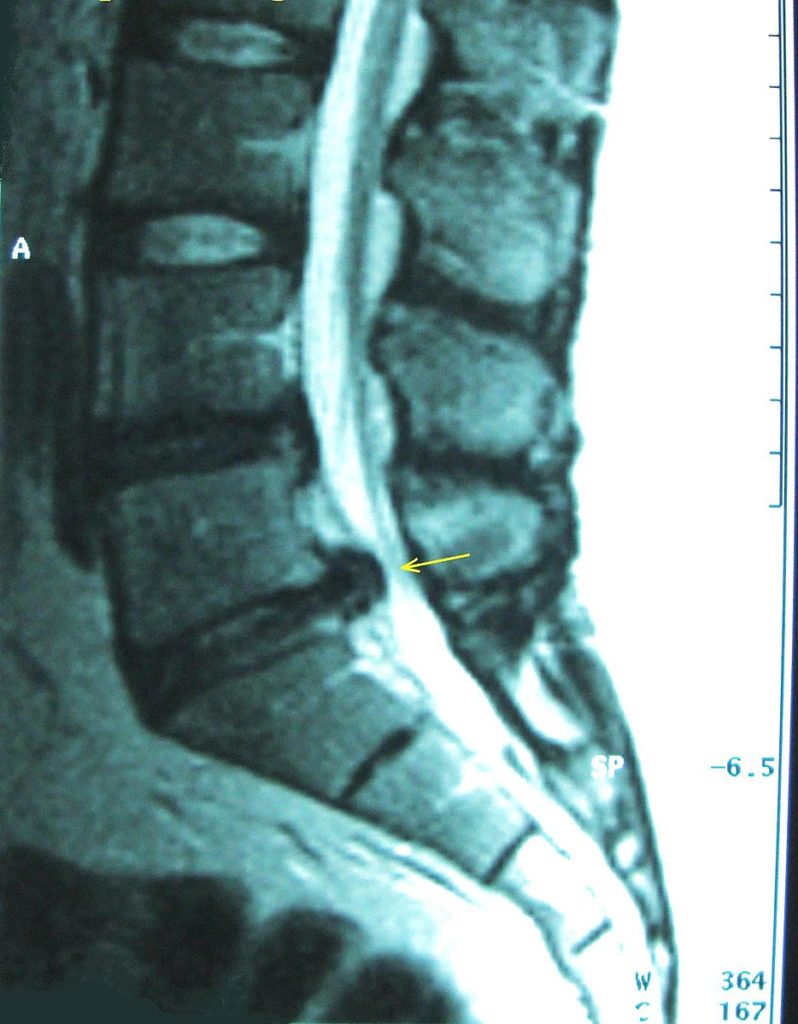

Bel omurgasında yer alan diskler, omurlar arasında yük taşıyan ve hareketi kolaylaştıran yapılardır. Diskin dış tabakasının zayıflaması veya yırtılması sonucu iç kısmın dışarı doğru taşmasıyla bel fıtığı (lomber disk hernisi) oluşur. Bu durum, omurilikten çıkan sinir köklerine baskı yaparak ağrı ve nörolojik şikâyetlere neden olur.

Bel fıtığında tanı, yalnızca MR görüntüsüne bakılarak konulmaz. Değerlendirme sürecinde:

- Manyetik Rezonans Görüntüleme (MR)

birlikte ele alınır. Amaç, görüntüleme bulguları ile hastanın şikâyetlerini birbirleriyle uyumlu şekilde değerlendirmektir.